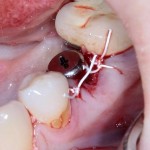

Немедленная имплантация — оптимальное решение в любой клинической ситуации